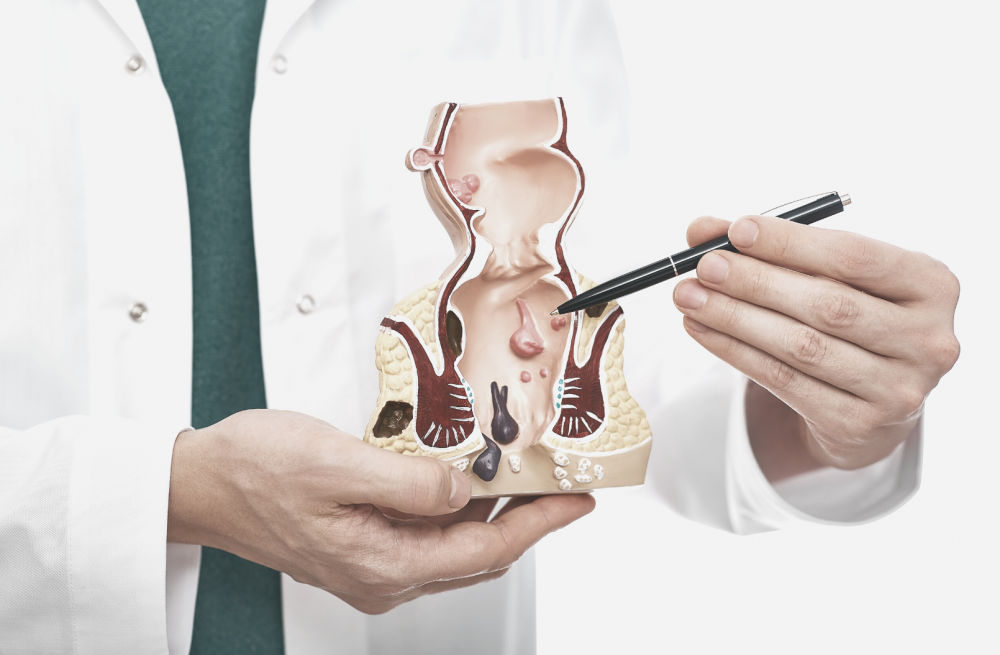

Плоскоклеточный рак анального канала

Плоскоклеточный рак анального канала (ПРАК) — редкий вид онкологических заболеваний, в этой зоне локализуются до 2% всех опухолей толстой кишки.